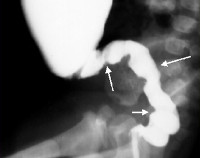

Q43.1 Болезнь Гиршпрунга